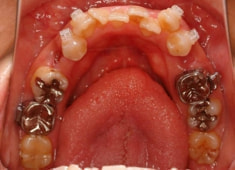

治療前